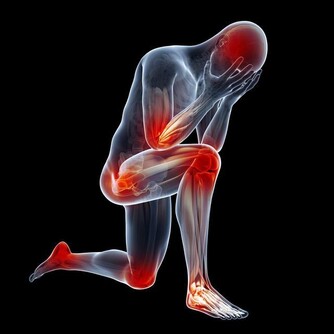

3、下肢水腫

晚上睡覺的時候身體裡面的尿酸含量是最高的,所以腎小球容易被堵塞,甚至會出現壞死情況,身體裡面的水分沒有辦法很好的排出,容易堆積在身體裡面,這樣就會出現水腫情況,特別是下肢水腫以及眼瞼水腫的情況是比較嚴重的。

4、腰疼

身體裡面的尿酸如果堆積很多,腎臟就會出現非常嚴重的負擔,容易導致腎結石問題出現,腎臟出現問題就會影響到腰部的健康,容易出現疼痛感覺,情況嚴重的話還容易導致失眠症狀出現,所以一定要特別注意。